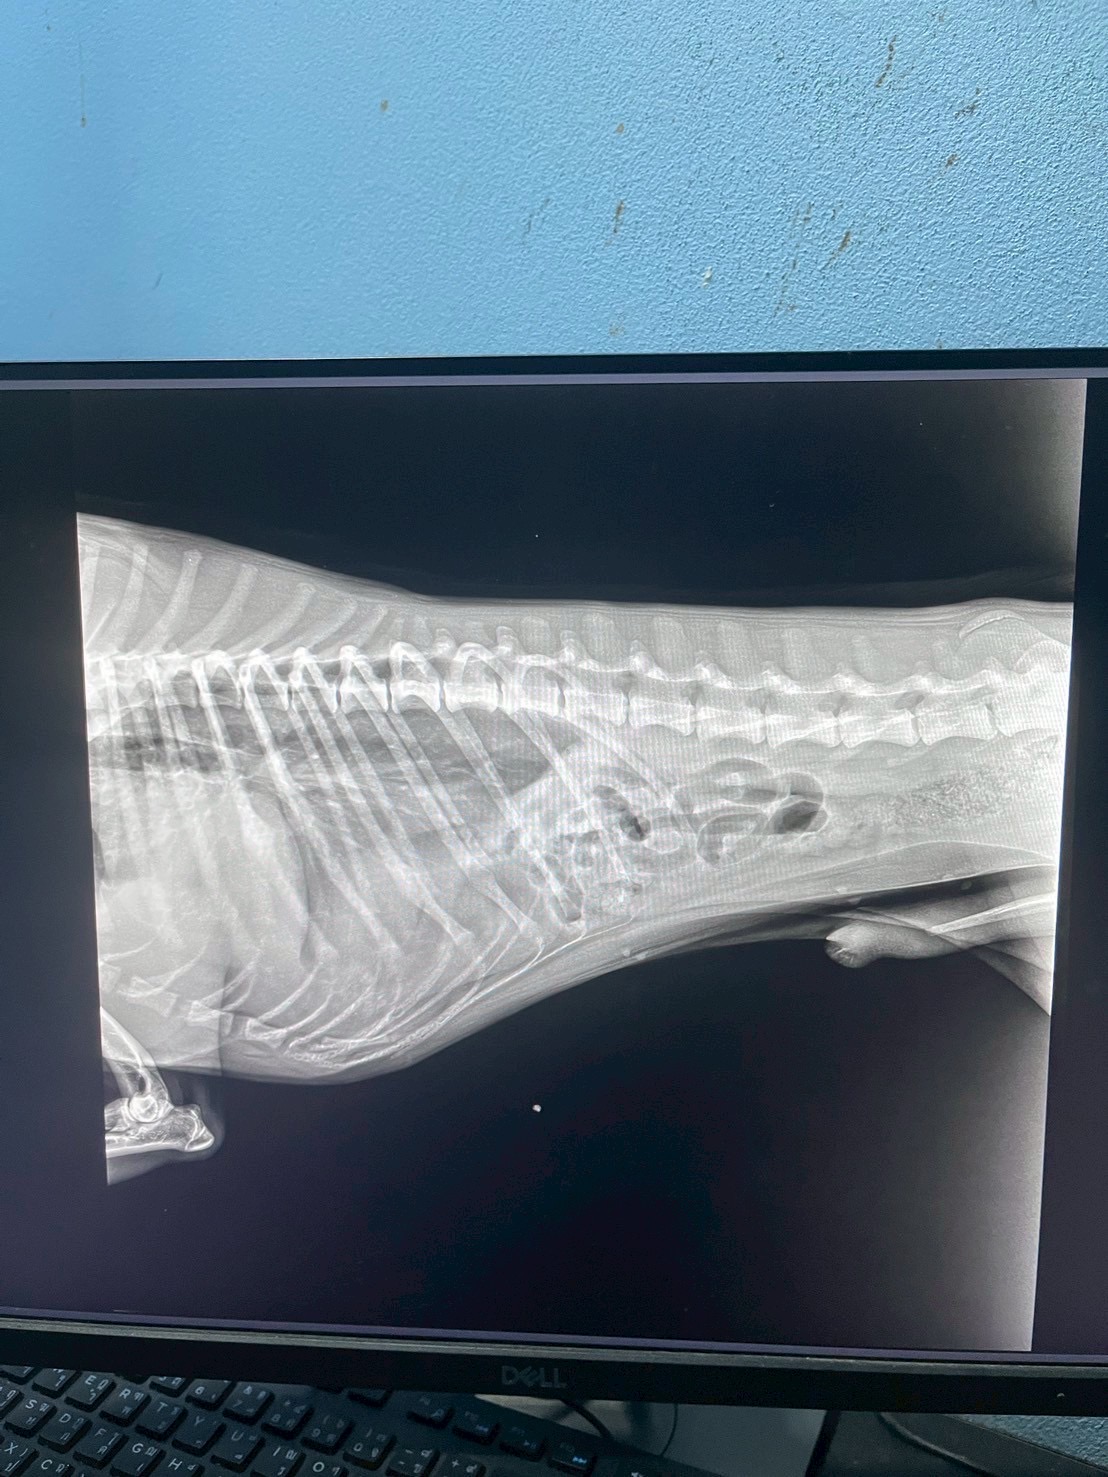

ทีมสัตวแพทย์ของเราได้รับเคสฉุกเฉินจากอุบัติเหตุที่ทำให้สัตว์เลี้ยงตัวหนึ่งได้รับบาดเจ็บรุนแรง กะบังลมฉีกขาดส่งผลให้อวัยวะในช่องท้องเคลื่อนเข้าไปในช่องอก ทำให้เกิดภาวะหายใจลำบาก หลังจากตรวจวินิจฉัยด้วยภาพรังสี ทีมสัตวแพทย์ได้ตัดสินใจเข้าผ่าตัดแก้ไขโดยการเย็บกะบังลม และจัดอวัยวะกลับสู่ตำแหน่งปกติ ผลลัพธ์เป็นที่น่าพอใจ น้องสามารถหายใจได้ตามปกติและกลับมาใช้ชีวิตได้อย่างมีความสุข โรงพยาบาลสัตว์ของเราพร้อมดูแลสัตว์เลี้ยงทุกตัวด้วยทีมแพทย์ผู้เชี่ยวชาญ หากพบอุบัติเหตุหรือภาวะฉุกเฉิน